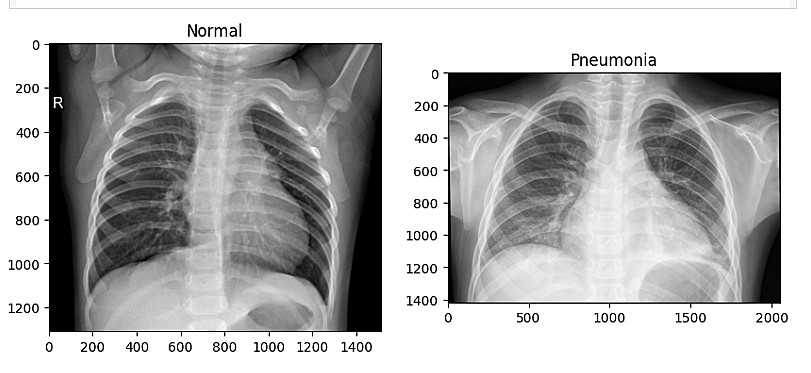

تحليل بيانات طبية مثل X-Ray أو Garbage Classification